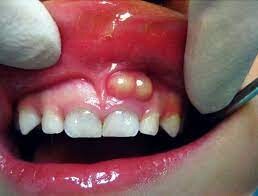

What Is A Tooth Abscess?

A tooth abscess is a bacterial infection found in the inner part of the tooth where pus has collected and can cause moderate to severe pain in people who suffer from the condition. Tooth abscesses can occur when a cavity has gone untreated for too long or when a crack or chip in the tooth allows bacteria to find its way into the dental pulp (the inner, soft part of the tooth) area of the tooth and gets infected.

Once the bacteria has made its way inside, it will spread down to the root and cause both inflammation and swelling. Once inflammation occurs, it will force the pus into a tight space (known as the abscess) at the tip of the root where the swelling exists.

Symptoms

Signs and symptoms of a tooth abscess include:

Persistent, throbbing or severe toothache

Extreme temperature sensitivity

Pain when performing normal chewing or biting

Fever

Swelling in the face or the cheeks

Lymph nodes under the jaw or in the neck become tender or swollen

A rush of foul-tasting fluid in the mouth followed by cessation of pain, which means the abscess has ruptured

If you experience any of the signs or symptoms listed above, you should see your dentist immediately, especially if you begin to experience swelling in your face or begin to feel feverish. If your dentist cannot see you immediately, you should go to an emergency room as it’s possible these symptoms indicate the infection is possibly spreading into your jaw and the surrounding tissue.

The only way to rid yourself of both the pain and the condition is to get proper dental treatment. You may feel a lessening of pain if the abscess ruptures, but you’ll still need to get a professional’s help. The infection could spread to other parts of your jaw and beyond to parts of your head and neck and, in a worst-case scenario, lead to sepsis, which is an infection throughout the entire body that can put your life at risk.

Tooth Abscess Treatments

Treating a tooth abscess involves draining the abscess and ridding the area of the infection. The tooth itself may be saved with a root canal treatment, but in some instances, it may need to be removed completely. Leaving a tooth abscess untreated can lead to serious, even life-threatening, complications. Your dentist or oral surgeon may recommend the following: